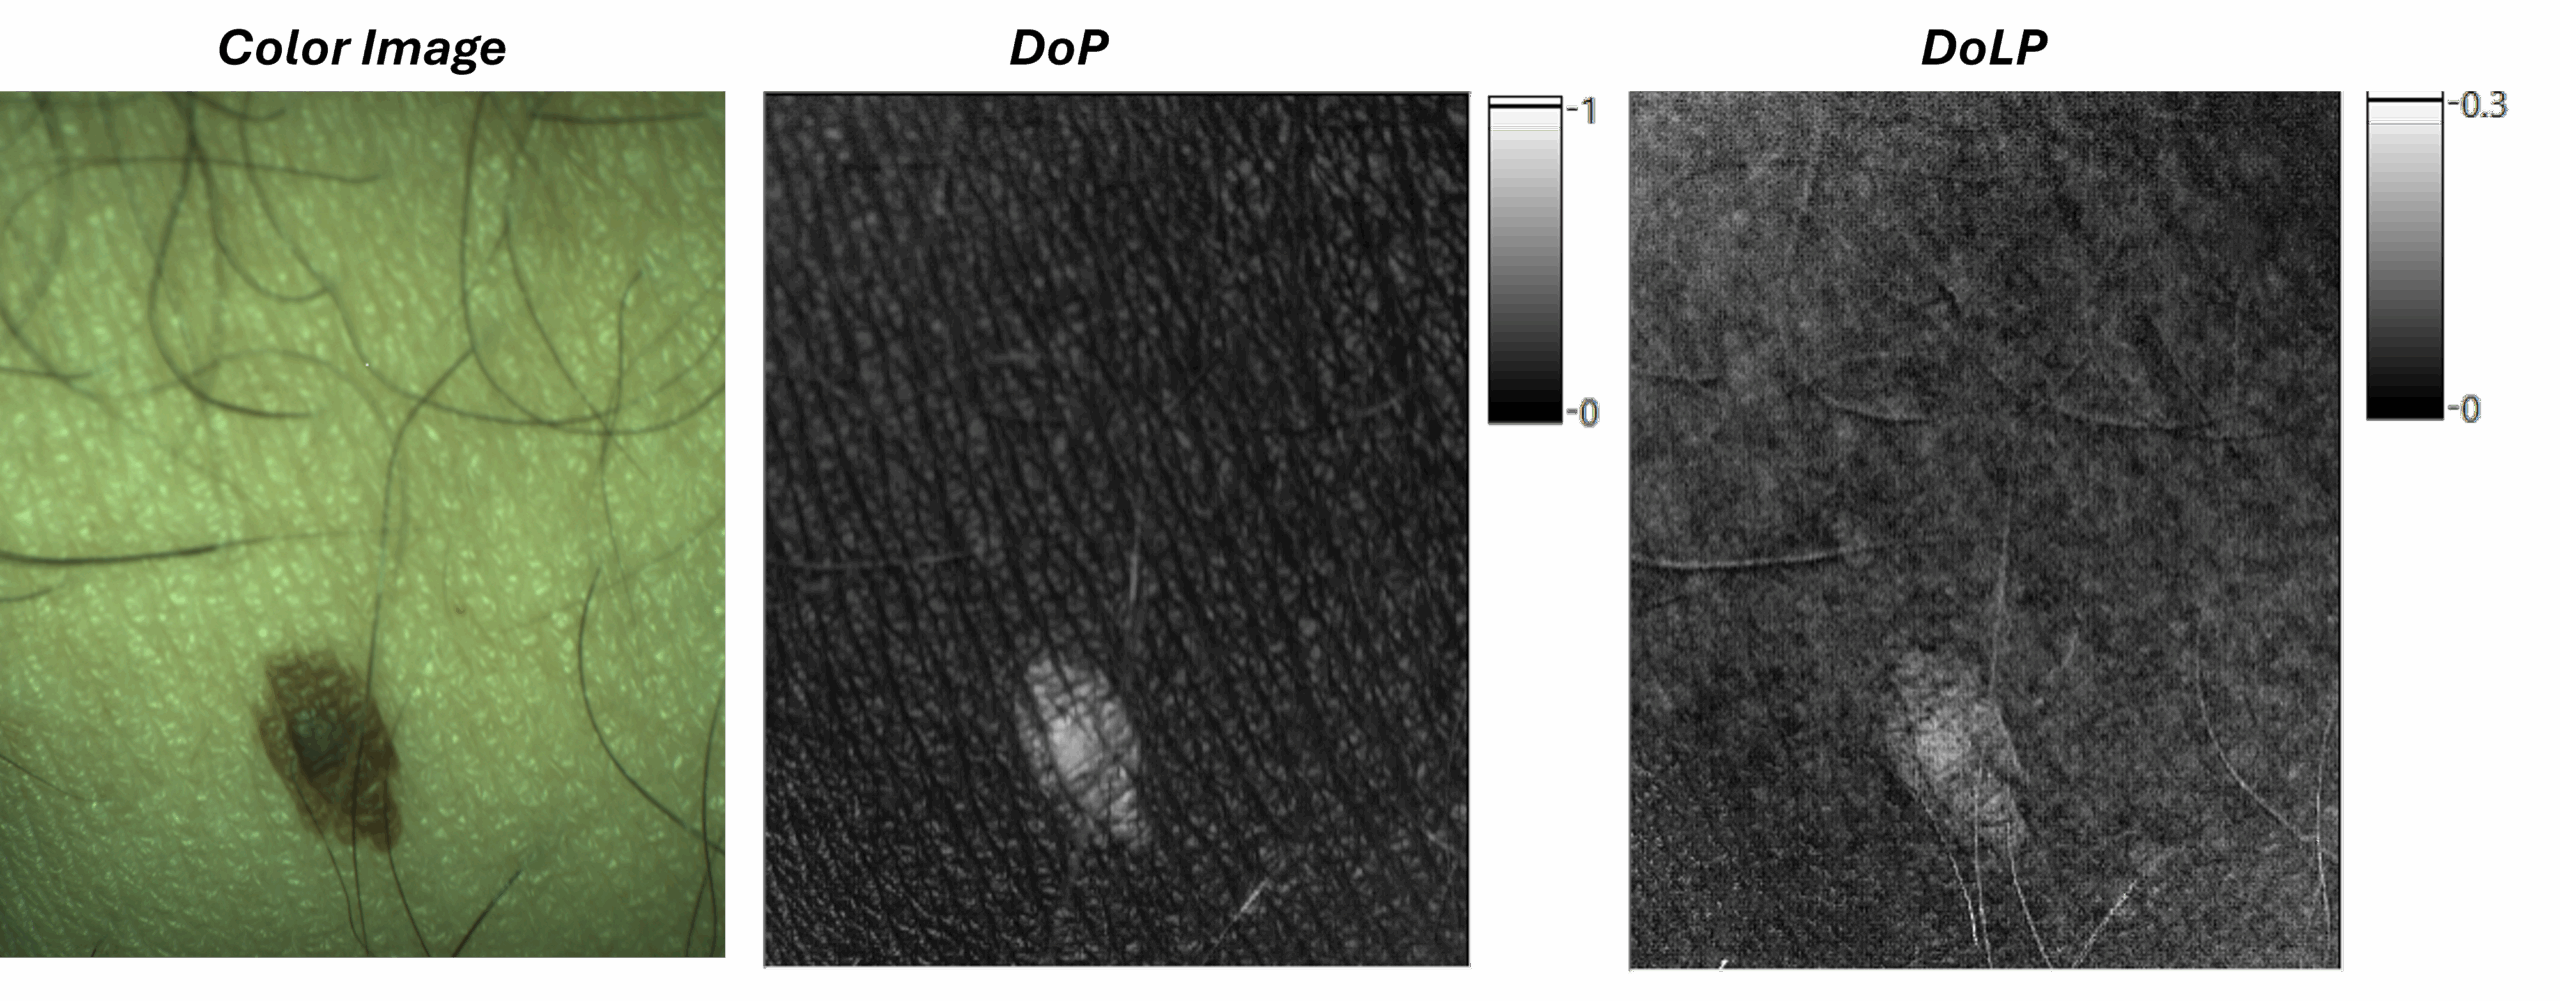

Quantitative Analysis of Skin Lesions

The Polvision Dermatoscope provides enhanced data to facilitate the differentiation of benign and malignant skin lesions. By analyzing a lesion’s complete polarization signature—the system can detect subtle changes in tissue architecture that are invisible to the naked eye.

Generally, high melanin content in a lesion (which will make it appears dark) increases the DoP. This occurs because melanin’s strong light absorption dramatically reduces multiple scattering which is the primary depolarizing effect. However, this DoP elevation will occur in both benign and malignant lesions, so additional contrast is needed.

- Benign Lesions (e.g., Nevi): These features are typically non-invasive. Even if highly pigmented (which will highly increases the DoP), they preserve the organized, birefringent collagen network of the dermis. This results in a significant high Degree of Linear Polarization (DoLP), indicating structural integrity. I.e. the collagen matrix will convert part of the incomming circular polarizated into linear polarization.

- Malignant Lesions (e.g., Melanoma): Malignancy is characterized by invasive, chaotic growth that actively degrades and destroys the dermal collagen network. This architectural breakdown causes a significant loss of birefringence and a corresponding low levels of DoLP signal (note that DoCP and DoP will be still high for heavily pigmented lesions).